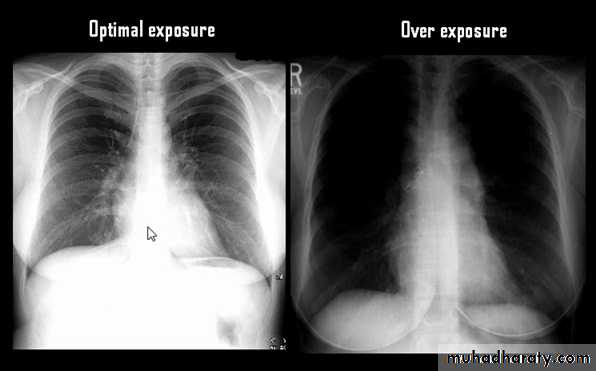

Techniques - Projection

P-A (relation of x-ray beam to patient)Supine view (AP)

Routine Examination includes

P-A view , Other supplementary views are done according to the case. So all Patients admitted to hospital should have P-A X-ray In standing erect view in complete inspiration